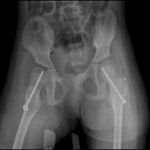

It is a dislocation which is not present at birth, but that develops progressively over the years and it is due to a number of factors such as spasticity, retraction of muscles, inappropriate muscle control, lack of load and unhealthy posture of patients affected by this condition.

These factors can trigger a process whereby the femur progressively moves away from its socket until complete dislocation, which occurs when the femoral head is completely out of the acetabulum and the two articular surfaces are no longer in contact with each other.

X-rays were aimed at measuring some indices that allow to establish the relationships between the femoral head and the acetabulum before surgery and after several year:

- the acetabular index (AI)

- the Migration percentage (MP)

- the femoral neck-shaft angle (NSA)